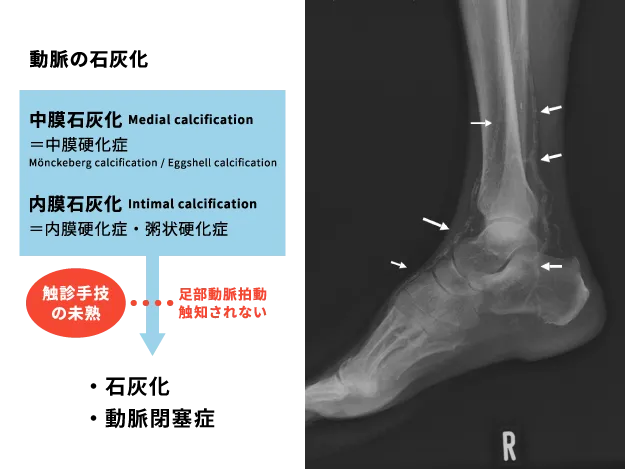

糖尿病のASOでは、膝下から足部の血管に強い石灰化(いわゆる石管化)を伴うため、血管移植手術は通常よりも難しくなります〈図6〉。しかし、医学的に手術が不可能な例はありません。

図9

図9. 下肢動脈の石灰化像

血管が石になっているため骨の様に血管が単純XPで描出される。(矢印)